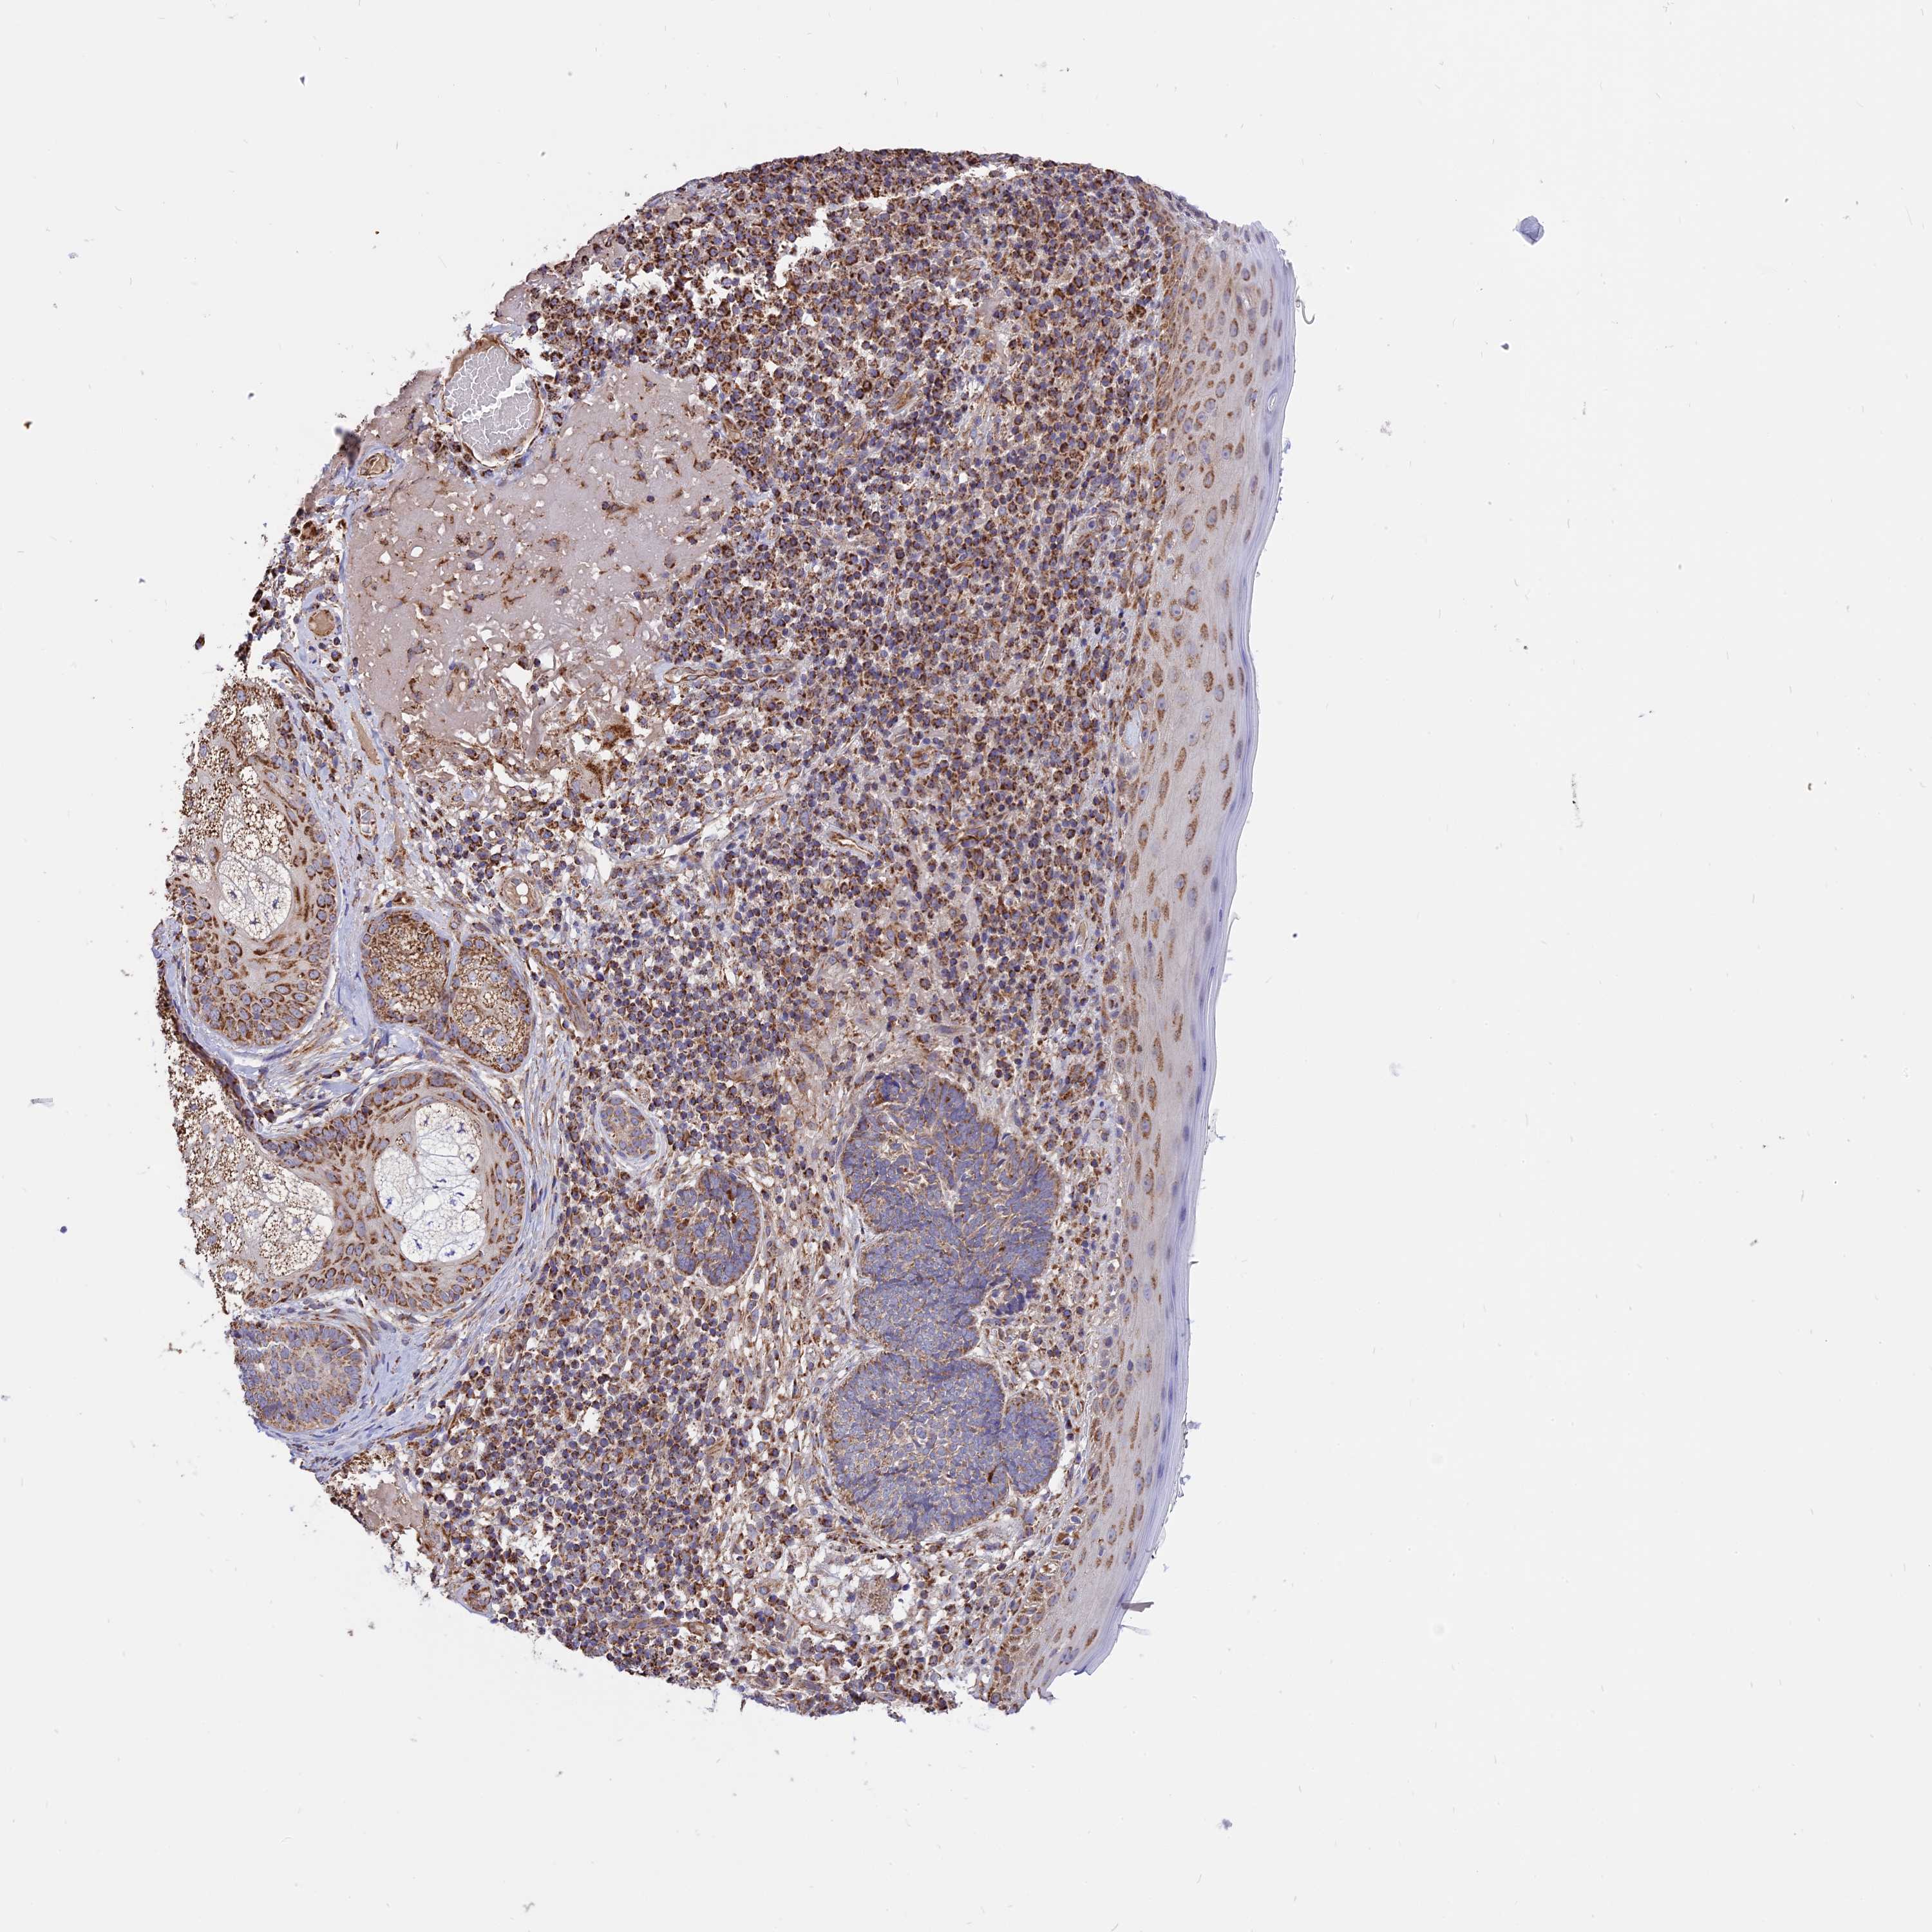

SKIN CANCER - Protein expressioni

A mouse-over function shows sample information and annotation data. Click on an image to view it in a full screen mode. Samples can be filtered based on level of antibody staining by selecting one or several of the following categories: high, medium, low and not detected. The assay and annotation is described here.

Each image is clickable and will lead to virtual microscopy that enables deeper exploration of all samples and also displays staining intensity scores, fraction scores and subcellular localization as well as patient and tissue information for each sample.

Antibody HPA041608

High

Intensity

Quantity

Location

Basal cell carcinoma